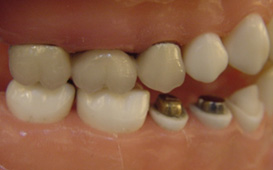

長牙橋導致蛀牙 - 案例二

拆下牙橋後